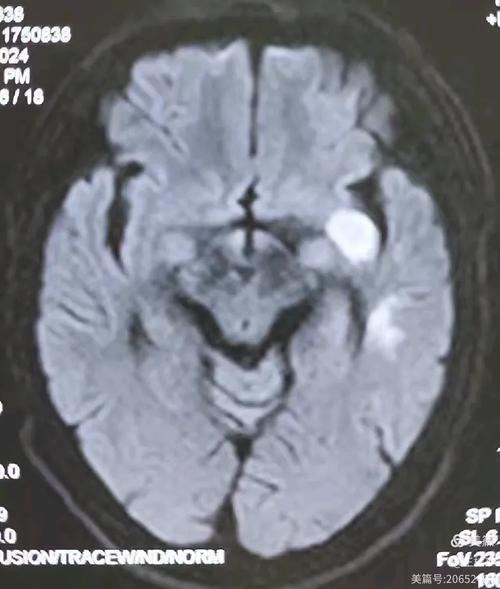

头颅MRI + DWI(弥散加权成像):

- 优点: 这是目前诊断早期脑梗死最敏感、最准确的方法,在发病后几十分钟到2小时内,MRI就能显示出缺血坏死的病灶,是诊断脑梗的“金标准”。